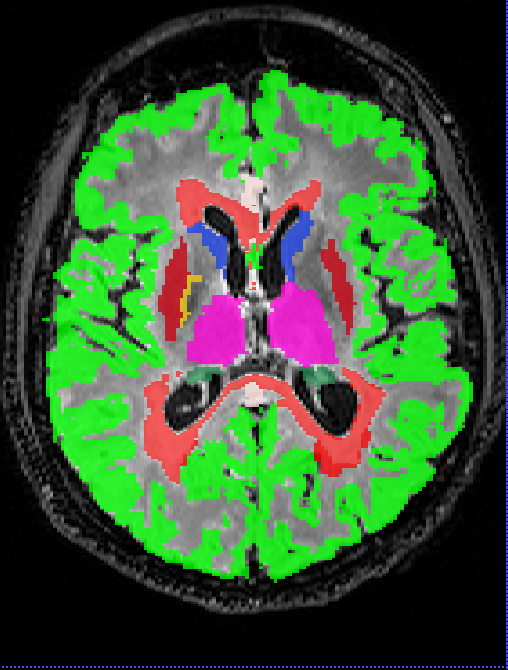

Performance metrics on the Insel32 dataset (vs the consensus segmentation) are summarised in Table 2, along with inter-rater comparison between the two raters, and between the raters and the consensus. An example of output of the methods considered, together with the manual ground truth, can be seen in Figure 2.

Box plots of the Dice coefficient for the segmentation (DeepSCAN multi-task) of various grey matter structures, when compared with Freesurfer, can be found in Figure 3. Both models performed quite robustly when applied to the Insel32 dataset. However, the nnUnet model can be seen to make substantial errors in the placing of structures on the MSSEG (out of sample) dataset, as can be seen in Figure 4.